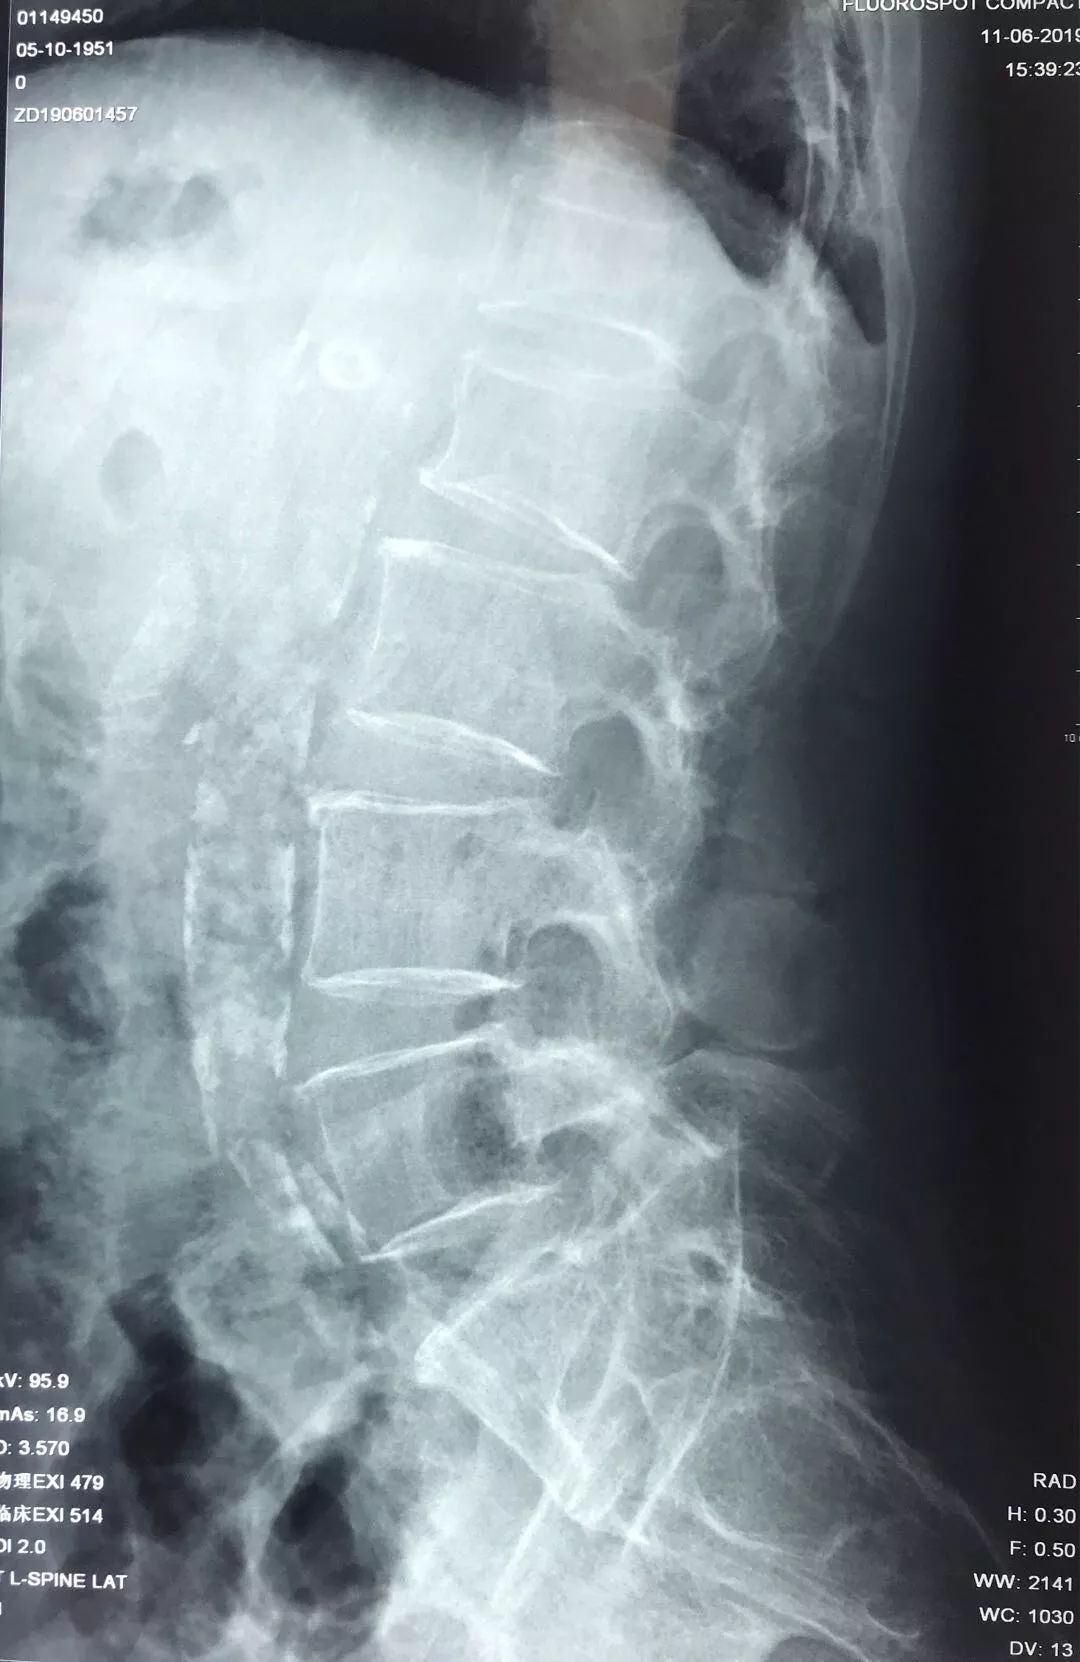

术前检查

检查时发现,患者T12陈旧压缩性骨折,L1椎体新鲜骨折。但胸椎MR:T1加权象T1椎体呈弥漫性低密度改变,不同于一般椎体压缩性骨折的局限性水肿表现。